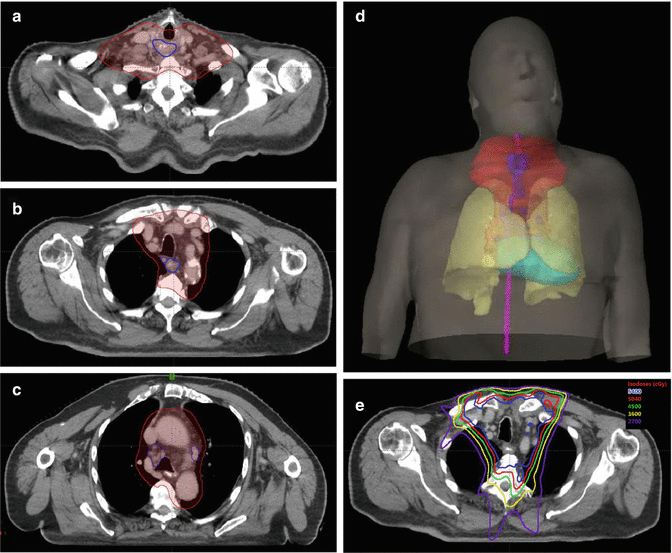

Compared clinical responses following 50.4 gy in 28 fractions and 60 gy in 30 fractions as a definite radiation dose based on the comprehensive registry of esophageal cancer in japan. Radiotherapy is an essential therapy for the patients with inoperable and locally advanced esophageal cancer (shridhar et al., 2013). We are skilled in providing targeted radiation therapy to save healthy tissue and improve our patients’ recovery times.

The course of radiation is five days a week, for five and half weeks. Using the latest technology, we can precisely target tumors and minimize damage to nearby healthy tissue. At present, definitive chemoradiotherapy is accepted as the standard treatment for locally advanced ec.

Hdr brachytherapy may be a useful salvage treatment. Radiation treatments can also be used to help patients manage their esophageal cancer. The ec guidelines recommend a radiation dose of 50.4 gy for definitive treatment, yet the outcomes for patients who have received.

The nonsurgical treatment for localized, deeply invasive esophageal cancer has been external beam radiation therapy (ebrt) and concurrent chemotherapy. Our radiation oncologists have years of experience safely and effectively treating esophageal cancer with radiation. The middle thoracic esophagus extends from.